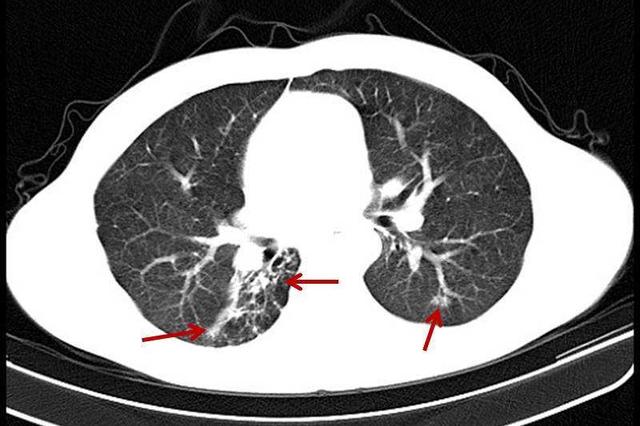

現在では、CT検査で肺に線維性病巣や石灰化病巣を見つけることは比較的日常的に行われている。 一般に、限局した筋状病巣や石灰化病巣は、その場所が古い病変であることを示しており、下図は左肺尖部に石灰化病巣を認めた患者の典型的なCT画像である。

最も一般的なのは肺の炎症や感染で、炎症性滲出液や全抗炎症過程における肺の限られた炎症や感染病巣が、慢性的な刺激の後、肺に局所的な線維性縞病巣を残すためで、縁の一部は胸膜を引っ張ることができる。CTやレントゲンでは、境界のはっきりしたやや高密度の影の線のように見えます。

結核が治癒した後は、結核が発生した肺の小葉や肺分節に限局した病巣が認められ、しばしば点状または結節状の石灰化病巣を伴う。二次性結核性胸膜炎の場合、胸膜に沿って大きな石灰化病巣が存在することがあることを付記しておく。